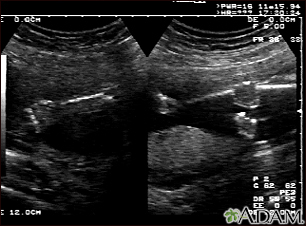

Ultrasound, normal fetus - arms and legs